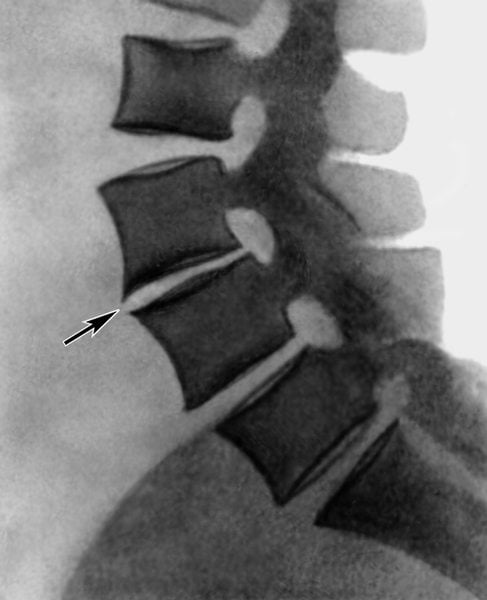

Остеоартроз периферических суставов диагностируется по характерным клиническим признакам. Врач изучает анамнез пациента, в котором могут быть указаны предшествующие травмы, эндокринные патологии, заболевания, спровоцированные нарушениями обмена веществ. Симптомы остеоартроза похожи на клинические проявления некоторых суставных патологий: артрита, бурсита, остеохондроза. Поэтому проводятся дифференциальные инструментальные исследования. Наибольшей информативностью отличается рентгенография. На снимках, сделанных в двух проекциях, хорошо заметны дегенеративно-дистрофические изменения в суставных сочленениях и позвоночнике:

- сужение суставной щели;

- деформация и истончение костной площадки;

- формирование кист;

- разрастание костных тканей, образование остеофитов;

- подхрящевое уплотнение тканей.